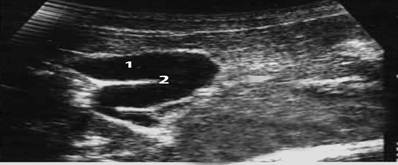

Конкремент представляет собой гиперэхогенное образование с четкими не всегда ровными контурами, смещается по стенке желчного пузыря при изменении положения тела пациента. Немаловажным симптомом является наличие акустической дорожки позади конкремента. Приводим наблюдение (рис 1).

Рис.1 Сонографическая картина холедохолитиаза

Пациент Л. 36 лет. На сонограмме определяется:

1. Желчный пузырь

2. Конкремент в полости желчного пузыря

3. Неравномерное утолщение стенки желчного пузыря

4. Акустическая тень

5. Симптом дорсального усиления эхосигнала

Диагноз: холелитиаз K80.0